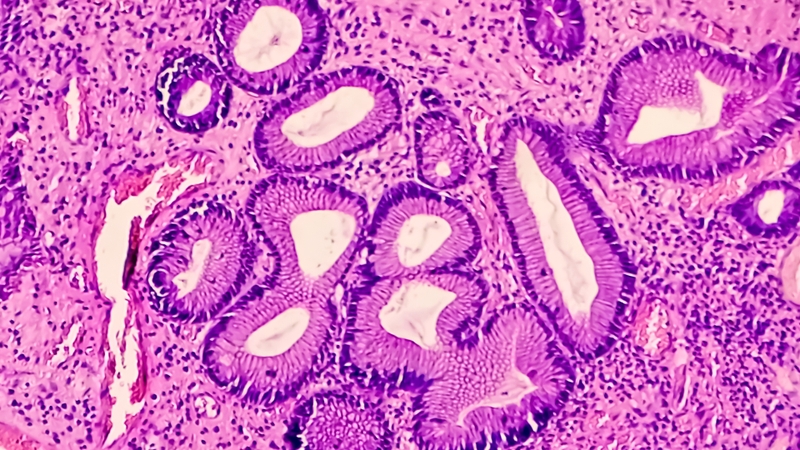

Các loại polyp dạ dày thường gặp

Polyp dạ dày có nhiều dạng khác nhau, mỗi loại mang đặc điểm và mức độ nguy hiểm riêng. Dưới đây là những dạng polyp phổ biến mà bạn nên biết.

Polyp tuyến phình vị

Polyp tuyến phình vị là dạng thường gặp nhất trong các loại polyp dạ dày, chiếm gần một nửa số trường hợp. Chúng thường nhỏ, không cuống, và hay xuất hiện ở phần phình vị hoặc thân dạ dày. Loại polyp này liên quan nhiều đến việc dùng thuốc ức chế bơm proton (PPI) kéo dài, như thuốc trị trào ngược. Dù ít nguy hiểm, polyp lớn hơn 1cm hoặc có dấu hiệu loét cần được cắt bỏ để kiểm tra thêm.

Polyp tăng sản

Polyp tăng sản khá phổ biến, thường hình thành ở những vùng niêm mạc bị viêm lâu ngày, đặc biệt do vi khuẩn Helicobacter pylori (HP). Dù thường lành tính, loại polyp này có thể tăng nguy cơ ác tính nếu kích thước lớn hơn 5mm hoặc đi kèm viêm teo niêm mạc. Vì thế, bác sĩ thường khuyên cắt bỏ và theo dõi định kỳ.

U tuyến dạ dày

U tuyến là dạng đáng lo nhất trong các loại polyp dạ dày vì được xem là tổn thương tiền ung thư. Chúng có thể gây chảy máu hoặc tắc nghẽn nếu phát triển lớn. U tuyến cần được cắt bỏ qua nội soi hoặc phẫu thuật, và người bệnh nên nội soi mỗi năm để kiểm tra nguy cơ ung thư, đặc biệt nếu có viêm teo niêm mạc.

Các loại polyp dạ dày: Dấu hiệu nhận biết và mức độ nguy hiểm 2

Mỗi dạng polyp dạ dày đều có đặc điểm riêng, ảnh hưởng khác nhau đến sức khỏe tiêu hóa của bạn